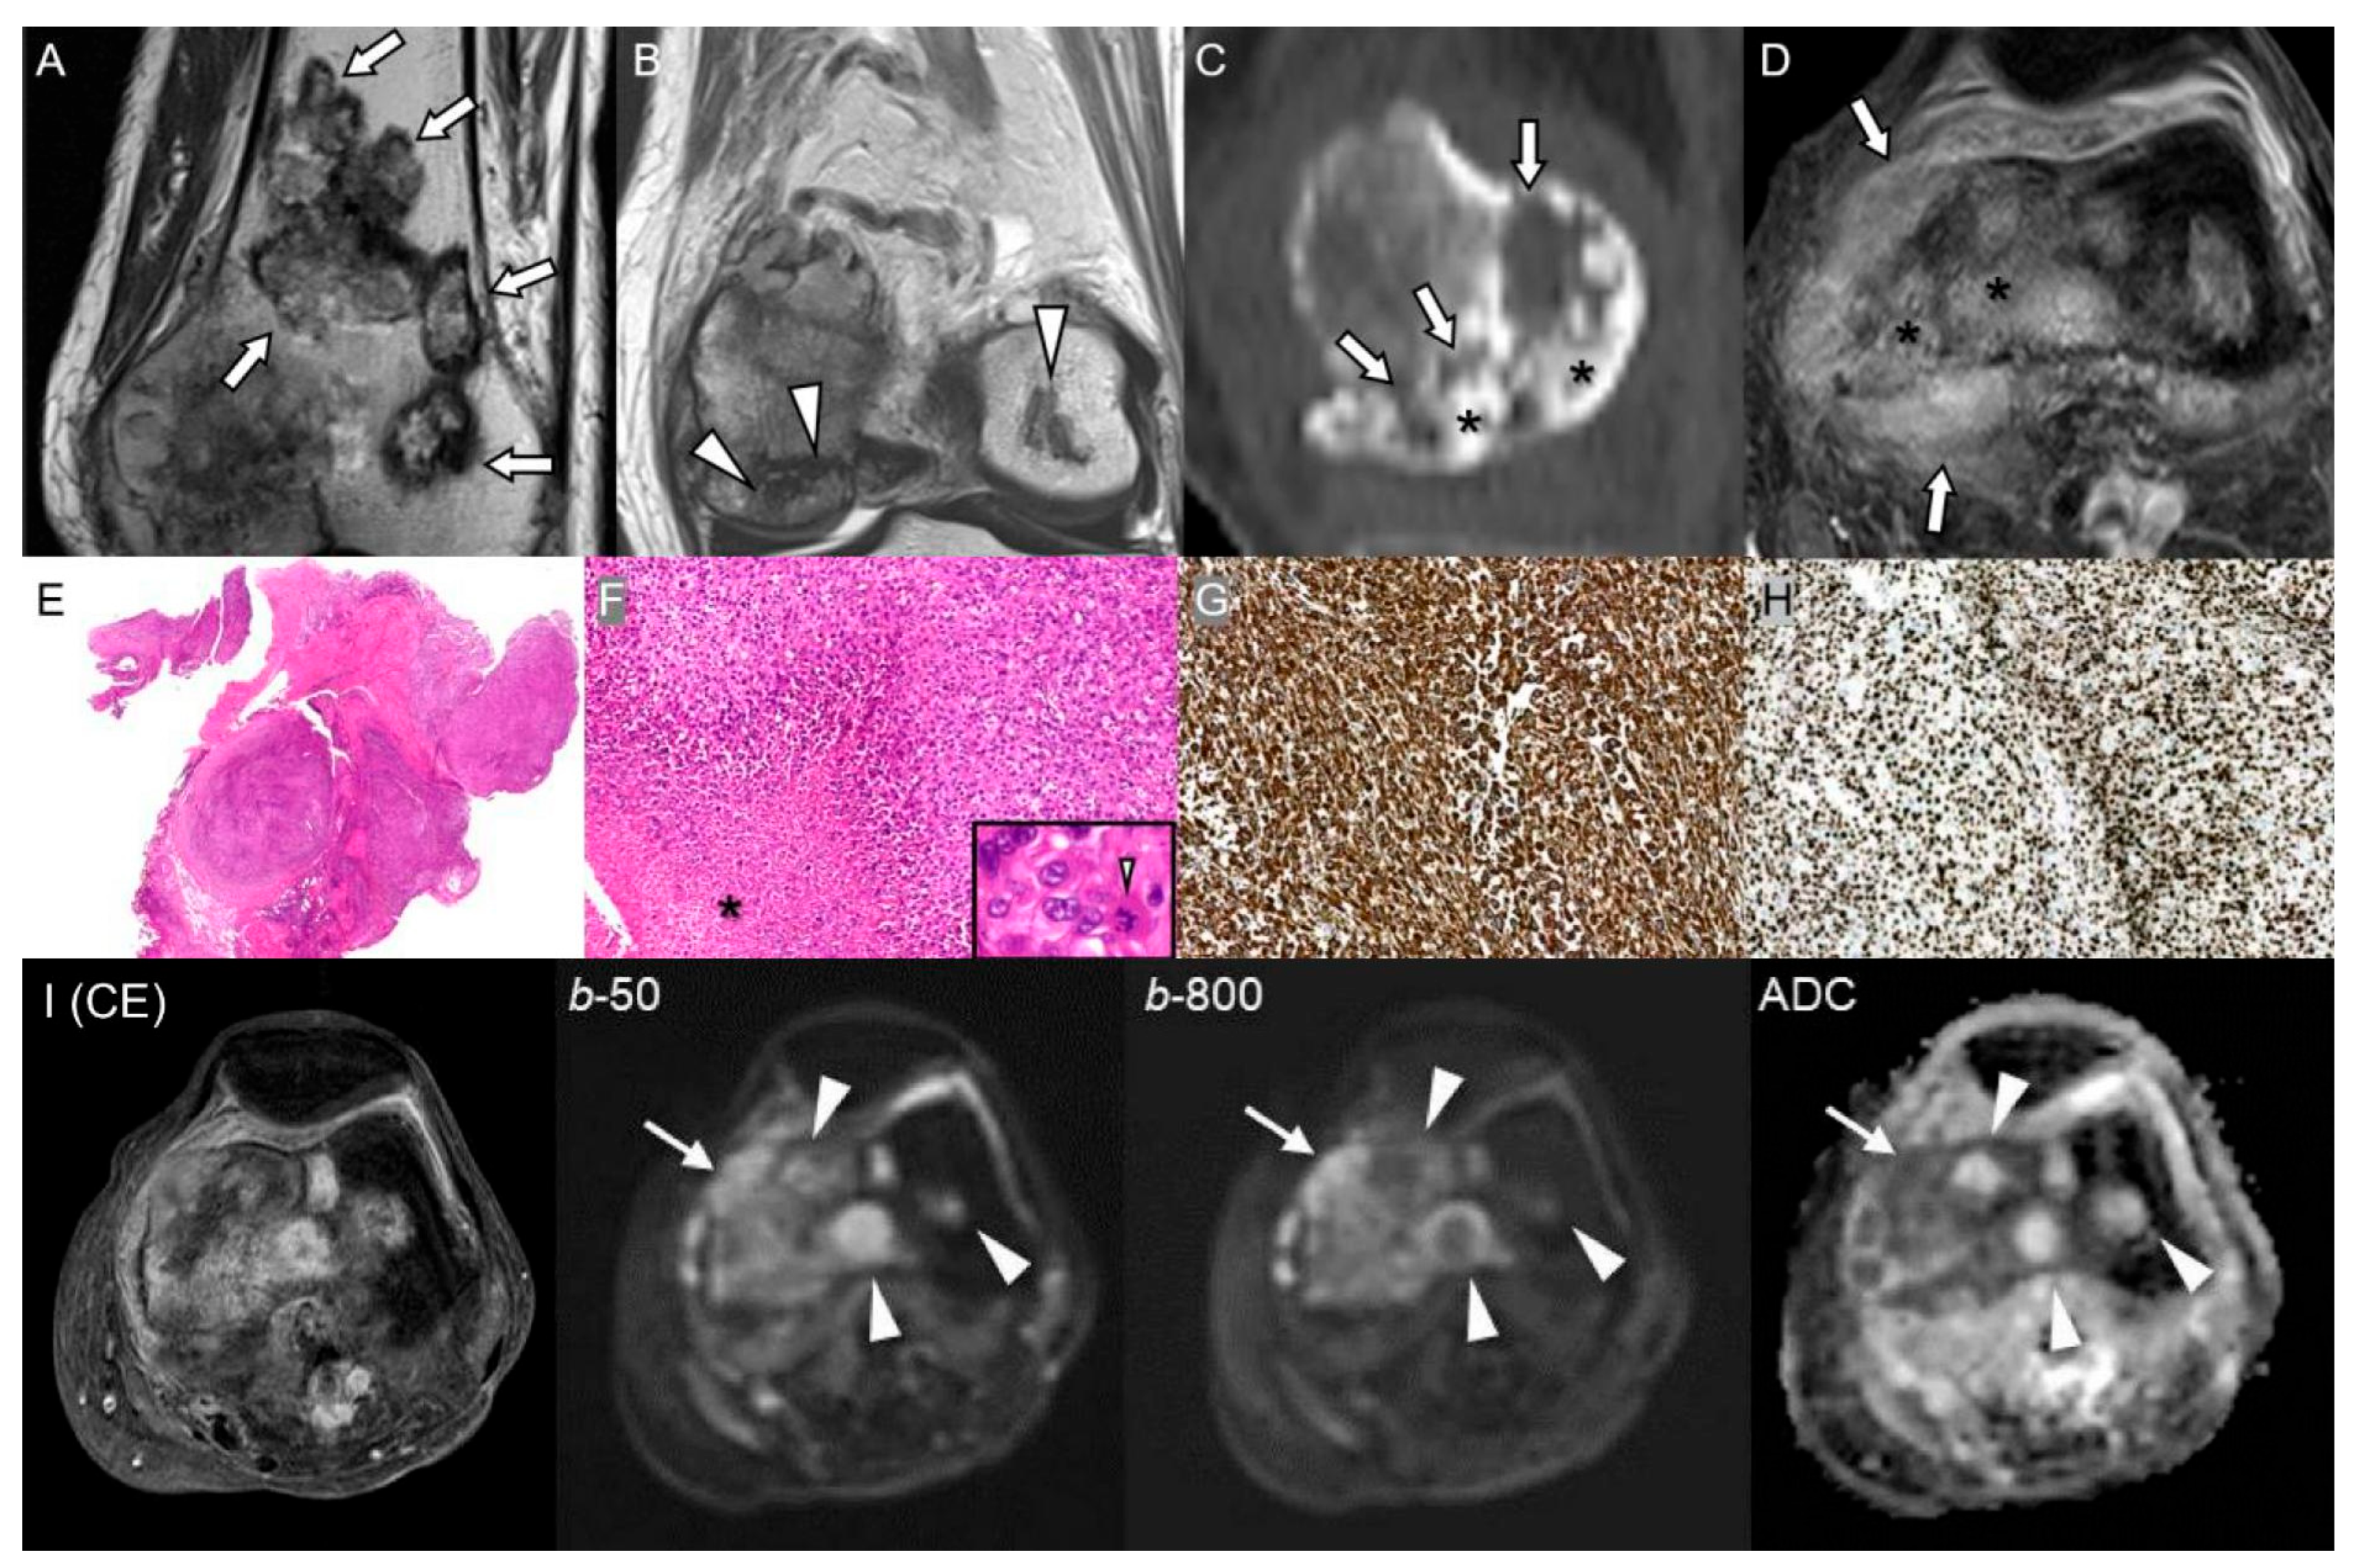

2.3. Giant Cell Tumor of Bone